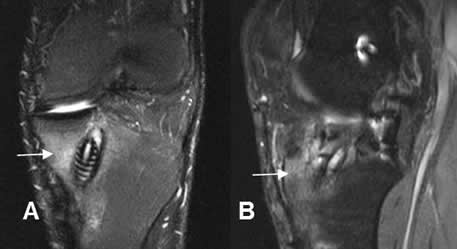

A y B: RM coronal en T2. Aunque no son pacientes con trauma, se muestran cambios por osteonecrosis. Signo del doble halo con reborde hiperintenso en T2, específico de esta patología.

Fig 136 A. Infección.

A: RM Coronal en STIR y B: RM sagital en STIR. PostQx de reconstrucción del LCA. Hay salida de material purulento por el orificio del túnel tibial y edema de la microtrabécula, por osteomielitis. (Flecha delgada).